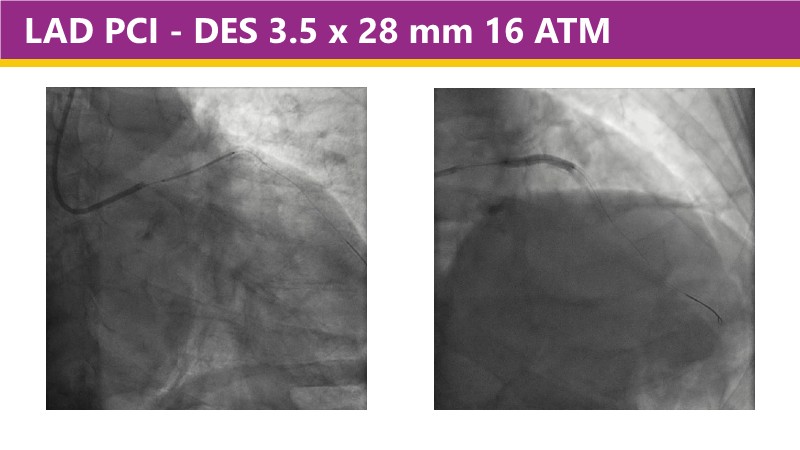

This EuroPCR 2025 session shares real-world insights confirming the promising results of the PINNACLE I trial, with LithiX IVL proving safe and effective across eccentric, concentric, and nodular calcifications.

Learn how this technology works, review the supporting evidence, and follow step-by-step case examples demonstrating optimal stent expansion and an efficient calcium modification workflow in daily practice.